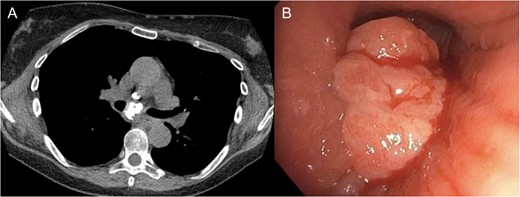

The patient was a 66-year-old white female with history of Histoplasmosis capsulatum infection and diabetes who presented as an outpatient with hemoptysis for 6 weeks. The patient was a lifelong non-smoker. A computer tomography (CT) scan of the chest revealed a calcified subcarinal lymph node along with an obstructing endobronchial lesion on the medial wall of the right mainstem bronchus (Fig. 1A). A rigid bronchoscopy was performed revealing an endobronchial mass causing a 50% obstruction of the right mainstem bronchus (Fig. 1B). The cryotherapy probe was used for mass excision and a full mediastinal staging was performed using endobronchial ultrasound (EBUS) bronchoscopy. The right mainstem bronchus was recanalized with return to 100% patency. Histology from the mass revealed an inflammatory polyp. The etiology of the inflammatory polyp was presumed to arise from inflammation stemming from the calcified station 7 lymph node abutting the medial wall of the right mainstem bronchus.

(A) Calcified subcarinal lymph node. (B) Obstructing endobronchial lesion on the medial wall of the right mainstem bronchus.